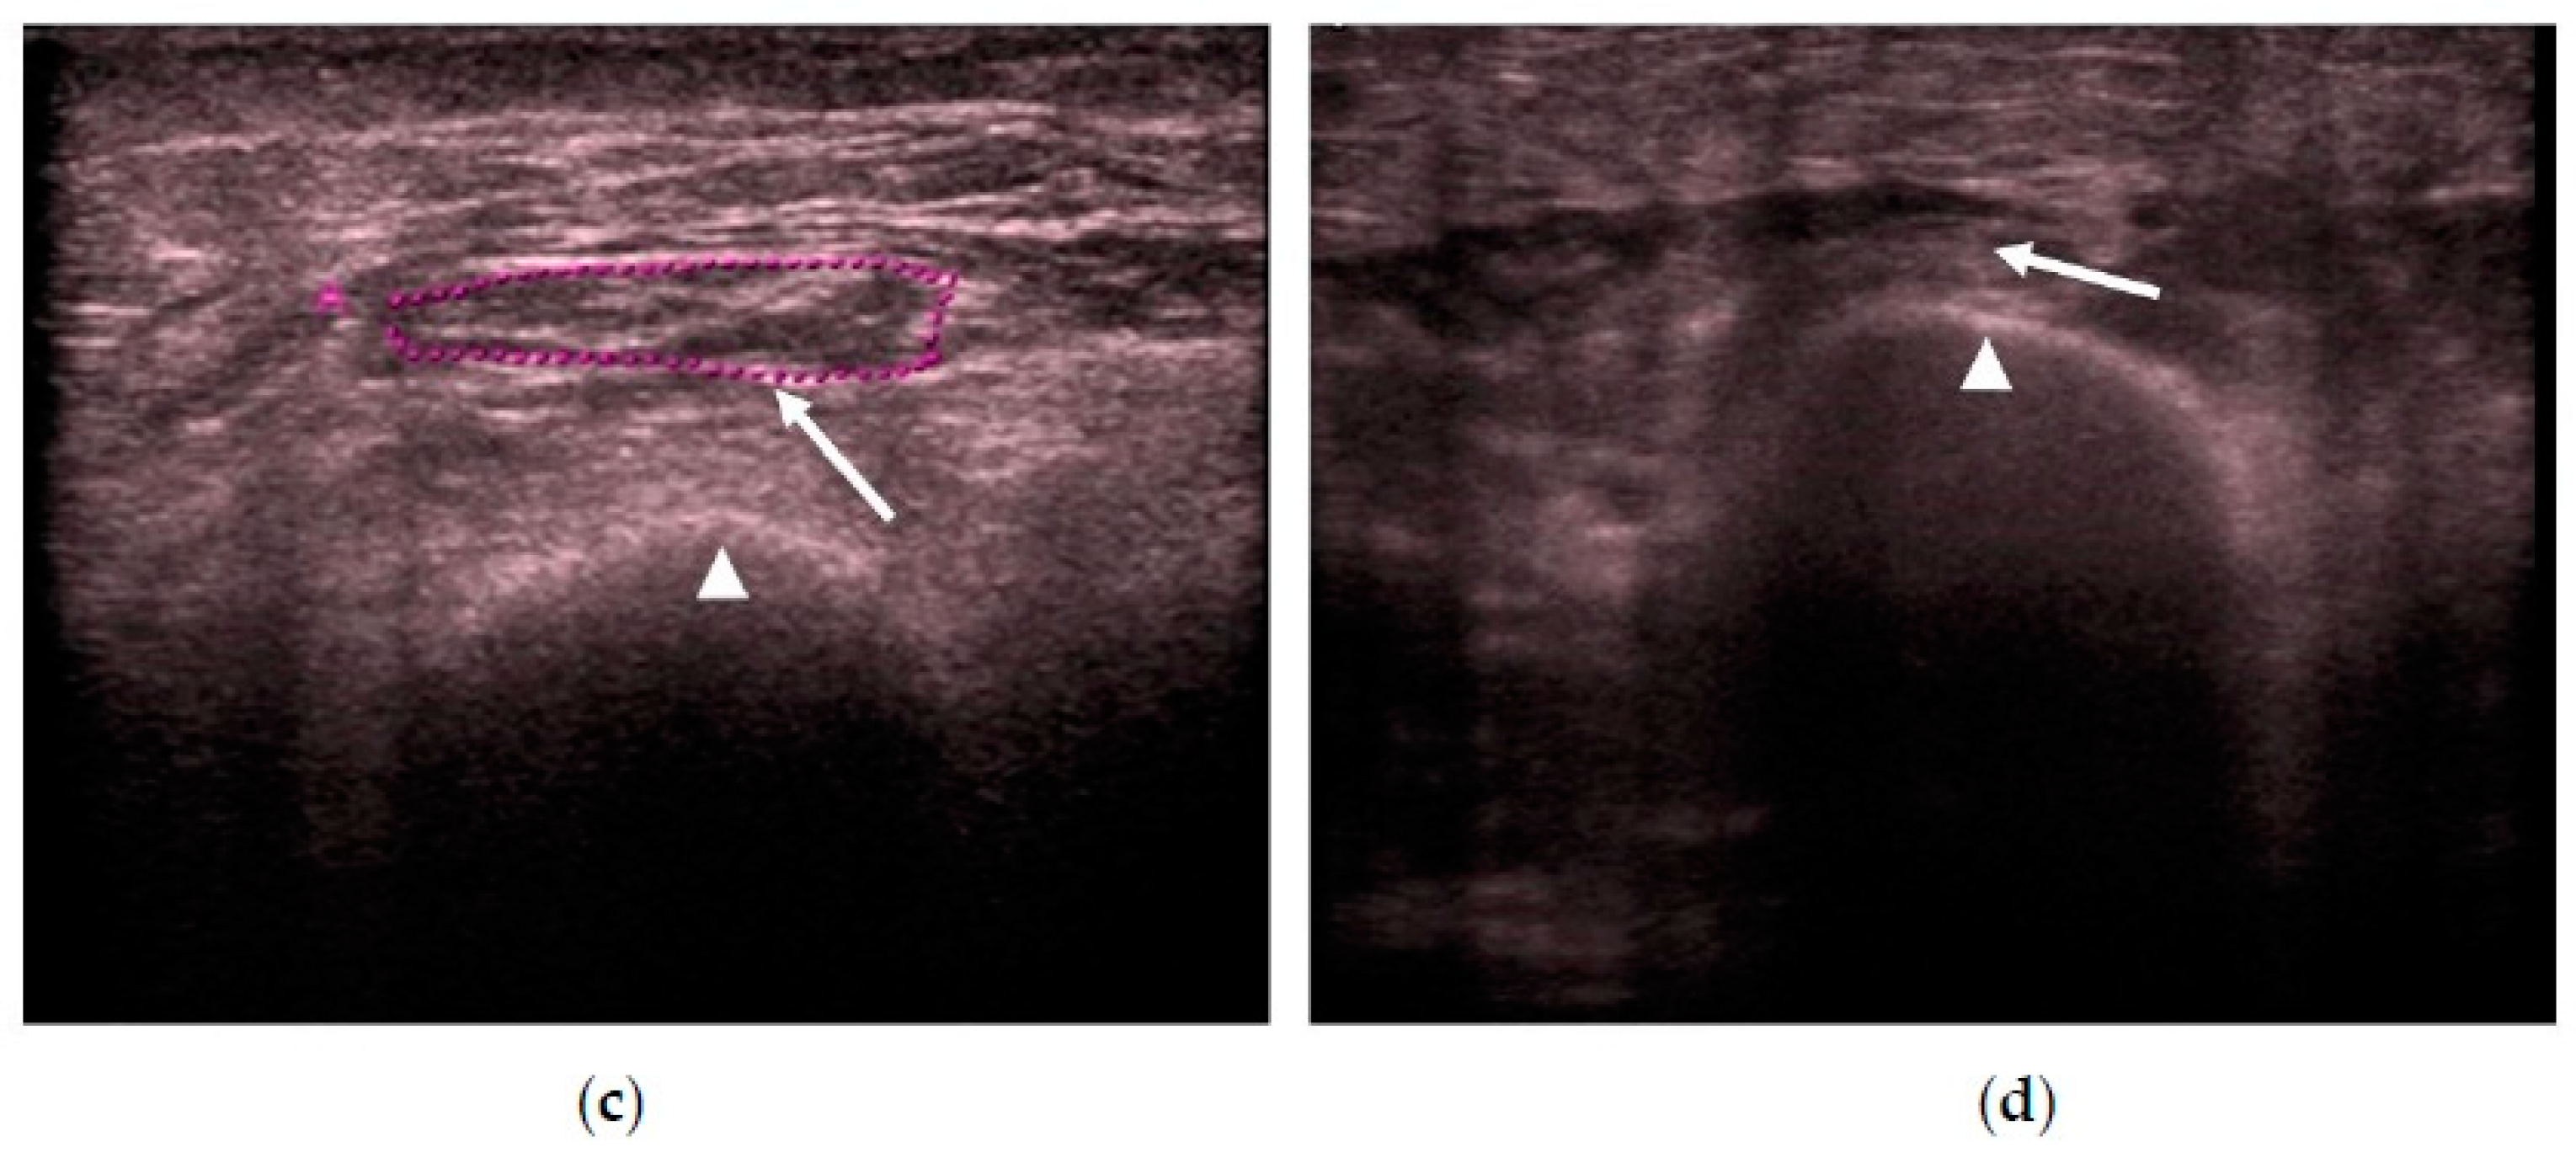

2.2. New Quadriceps Rectus Femoris Ultrasonography Assessment Protocol